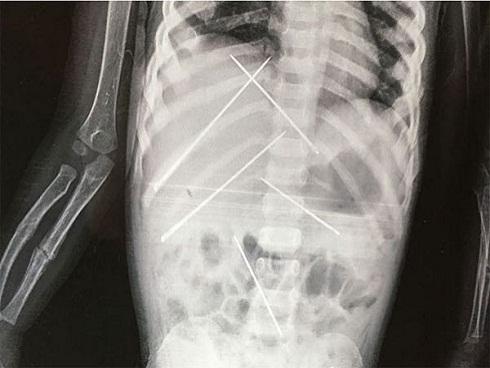

Bé gái 3 tuổi tử vong do bị ông chủ của mẹ đâm kim làm phép

Trong cơ thể cô bé bị coi như "hình nhân thế mạng" có 7 chiếc kim khâu dài 5 cm và cùng dấu hiệu bị tấn công tình dục.